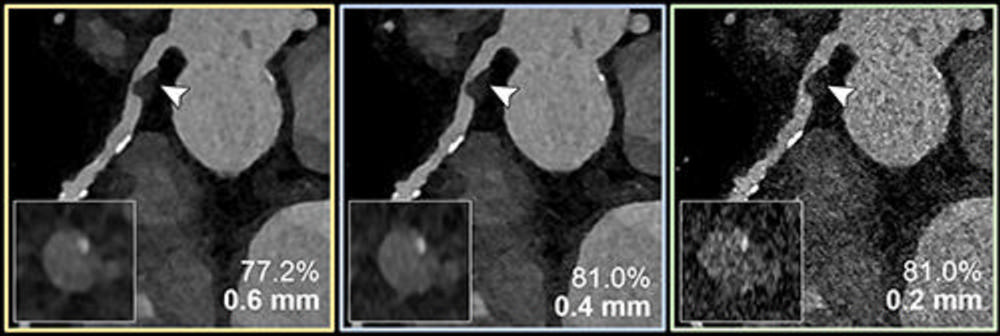

Figure 4. Coronary CT angiography for the suspected progression of known coronary artery disease in a 56-year-old female patient. Curved multiplanar reconstructions with 0.6-mm (yellow outline), 0.4-mm (blue outline), and 0.2-mm (green outline) section thickness show the respective calcified plaque (arrowheads) and coronary stenosis (inset images). The reduced section thickness leads to less calcium blooming and therefore a less severe assessment of percentage of coronary stenosis in this patient.